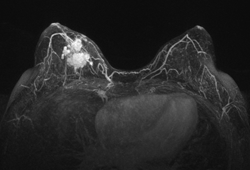

Silvia Formenti, M.D., radiation oncologist at New York University School of Medicine, presented research into the advantages of positioning breast cancer patients on their stomachs (prone) rather than on their backs (supine) during post-lumpectomy radiotherapy. Summarizing trials conducted at NYU, she said that using a prone position for treatment can enable a significant reduction in the volume of lung and heart tissue exposed to radiation for women with breasts of all sizes. "Prone positioning was optimal in sparing the lungs in virtually all right breast cancer cases, and for 85 percent of left breast cancer cases," she said.(1) Formenti also pointed out that research has shown the prone set-up reduces the amount of respiratory motion of the chest wall, which may further enhance the accuracy of targeting during treatment.(2) There is a contraindication, however; the prone set-up appears to be inadequate for breast cancer patients requiring radiotherapy to axillary lymph nodes.(3)